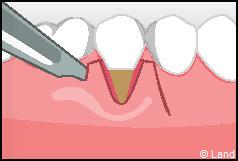

Les greffes de conjonctifs enfouis :

Destinées aux zones esthétiques, elles consistent à prélever la partie profonde du palais (site donneur).

Ce greffon est ensuite inséré sous la gencive au niveau de la récession (site receveur).